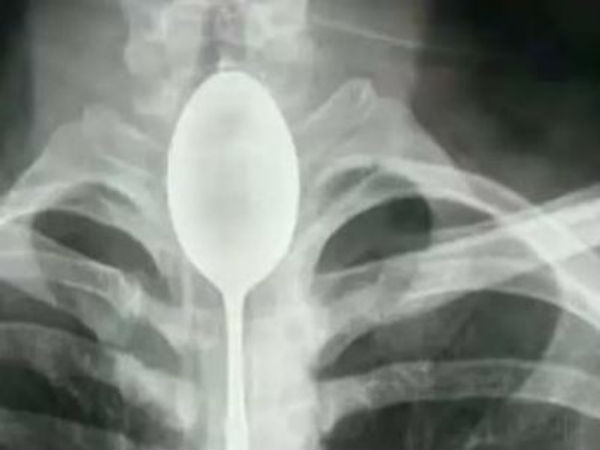

சீன இளைஞரின் அக்கப்போர்.. பிளாஸ்டிக் ஸ்பூனை விழுங்கி படாதபாடு!

ஒரு வருடமாக இளைஞரின் தொண்டையில் 20 செ.மீ. நீள ஸ்பூன் சிக்கியிருந்தது.

இப்படித்தான் ஒரு வருஷத்துக்கு முன்னாடி இவர் தனது நண்பர்களுடன் சேர்ந்து ஒரு விளையாட்டு விளையாடியுள்ளார். அந்த விளையாட்டு என்னவென்றால், ஒரு ஸ்பூனை அப்படியே விழுங்க வேண்டும் என்பதுதான்! இதற்காக 20 செ.மீ. நீளமுள்ள பிளாஸ்டிக் ஸ்பூனை விழுங்குவதாக பெட் கட்டப்பட்டது.

இப்போ பிரச்சனை என்னவென்றால் தொண்டை வலி கொஞ்சம் கொஞ்சமாக இளைஞருக்கு தெரிய ஆரம்பித்தது. பிறகு திடீரென மூச்சுக்குழலும் அடைத்துக் கொண்டது. இதனால் மூச்சுவிடவே ரொம்ப கஷ்டப்பட்டார். அதனால் சின்ஜியாங்கோல்மைன் என்ற மருத்துவமனைக்கு இளைஞர் கிளம்பி சென்றார். தன்னால் மூச்சுவிட முடியவில்லை, என்னன்னு பாருங்கள் என்று டாக்டர்களிடம் சொல்ல, டாக்டர்களோ எக்ஸ்ரே எடுத்து பார்த்தபோதுதான் தெரிந்தது மூச்சுக்குழலில் 20 செ.மீ. ஸ்பூன் இருந்தது!!

பேச முடியலையாம்

ஸ்பூனை தொண்டையில் பார்த்ததும் விக்கித்து நின்ற டாக்டர்கள், இப்படி ஒரு கேஸை வாழ்க்கையில் நாங்க பார்த்ததே இல்லை என்று சொல்லி, ஆபரேஷன் செய்து அந்த ஸ்பூனை வெளியே எடுத்தார்கள். ஆனால் ஆபரேஷன்தான் கொஞ்சம் கஷ்டமாக போய்விட்டதாம். இப்படி விபரீதமாகும்படி விளையாட்டு விளையாடியதால் வினை என்ன தெரியுமா? இளைஞருக்கு பேச முடியவில்லையாம்.